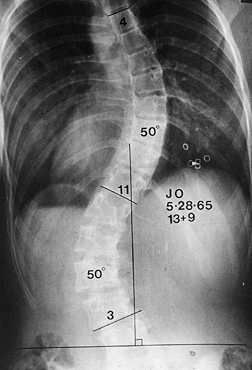

reported the long-term results of the Twin Cities Scoliosis Center’s

centered over the sacrum (Fig. 156.1, Fig. 156.2, Fig. 156.3, Fig. 156.4 and Fig. 156.5).

The lowest level of the fusion is established by drawing a line

this line is called the stable vertebra (Fig. 156.6). Ending the fusion at the stable vertebra gives uniformly good results.

Figure 156.2. Type II curve. The center sacral line has been created. The stable vertebra is T-12.